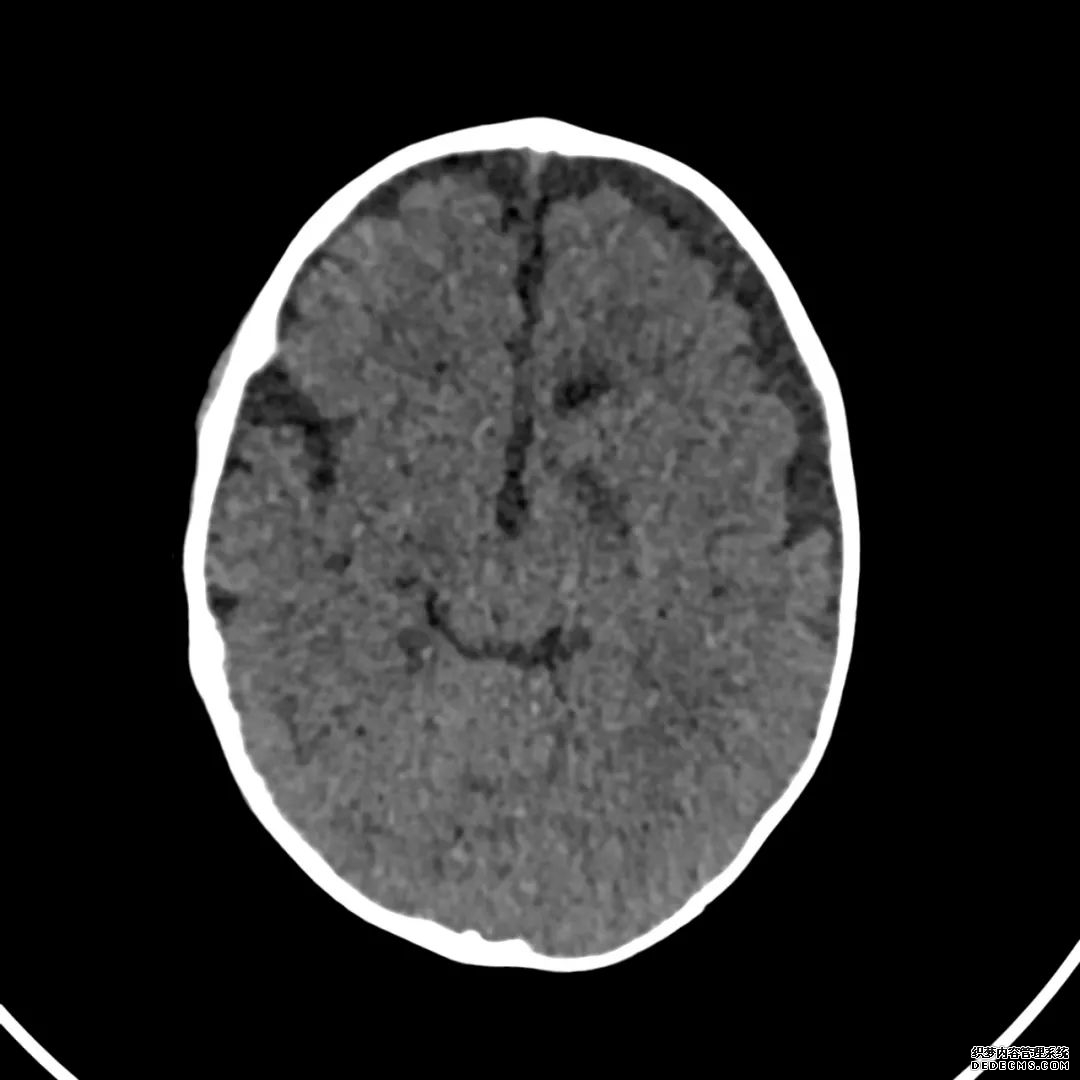

脑部CT检查显示扁豆状核内有略对称的低密度区。

脑MRI显示尾状核、扁豆状核和脑梗头部T2/FLAIR呈双侧对称异常高信号。扩散限制涉及这些区域,其特征是扩散加权DWI(B-1000)上的高强度,ADC图上相应的减弱强度。

印象:通过将这些成像模式与临床和实验室检查结果相结合,就有可能得出低血糖性脑病。

影像影响内囊后肢、大脑皮层(特别是枕叶和岛叶)、海马和基底节区,常是双边对称性的。